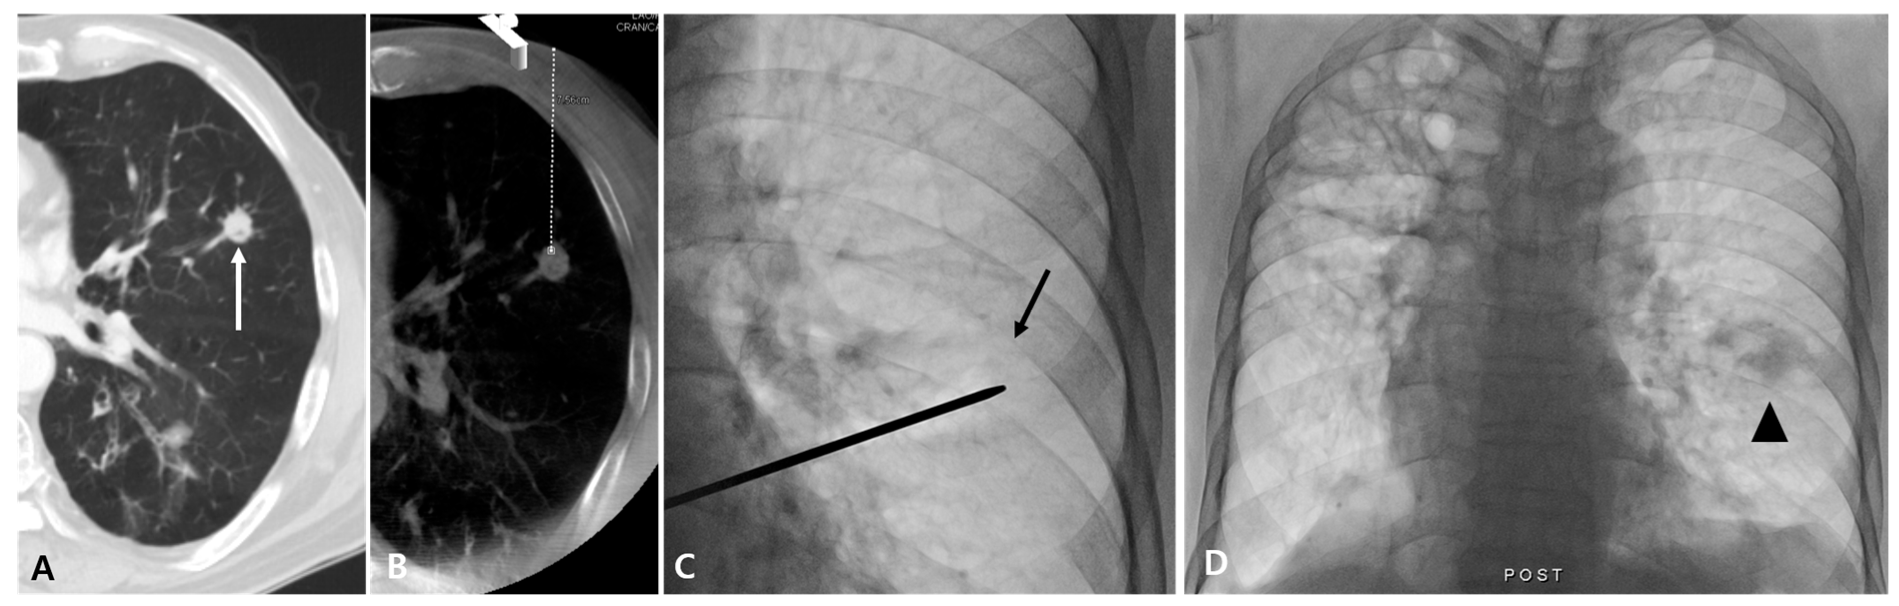

Figure 2.

Case of fluoroscopy-guided PTNB with the aid of planning CBCT of a lung nodule in a 79-year-old man with lung metastatic adenocarcinoma that resulted in a complication. A diagnostic CT image (A) and planning CBCT image (B) show an 11 mm nodule (white arrow) in the left upper lobe with a long aerated lung length achieved by needle insertion (46 mm). A lesion depth was 75.6 mm (white dashed line). On fluoroscopy, the nodule is identifiable (black arrow) (C), and PTNB was performed twice. After PTNB, hemoptysis occurred, and a post-PTNB fluoroscopic image shows peritumoral consolidation, representing a hemorrhage (arrowhead) (D).